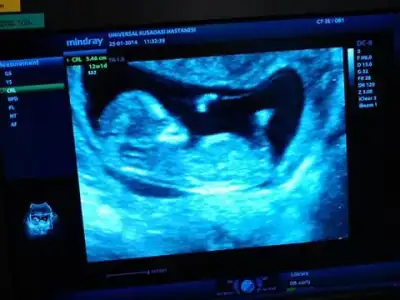

kızlar tecrübeli arkadaşlardan yorum rica ediyorum. doktorum%85-90 erkek dedi. henüz 12. haftamdayım. $2014-02-12 18.18.41.webp

kızlar tecrübeli arkadaşlardan yorum rica ediyorum. doktorum%85-90 erkek dedi. henüz 12. haftamdayım. Eki Görüntüle 977889